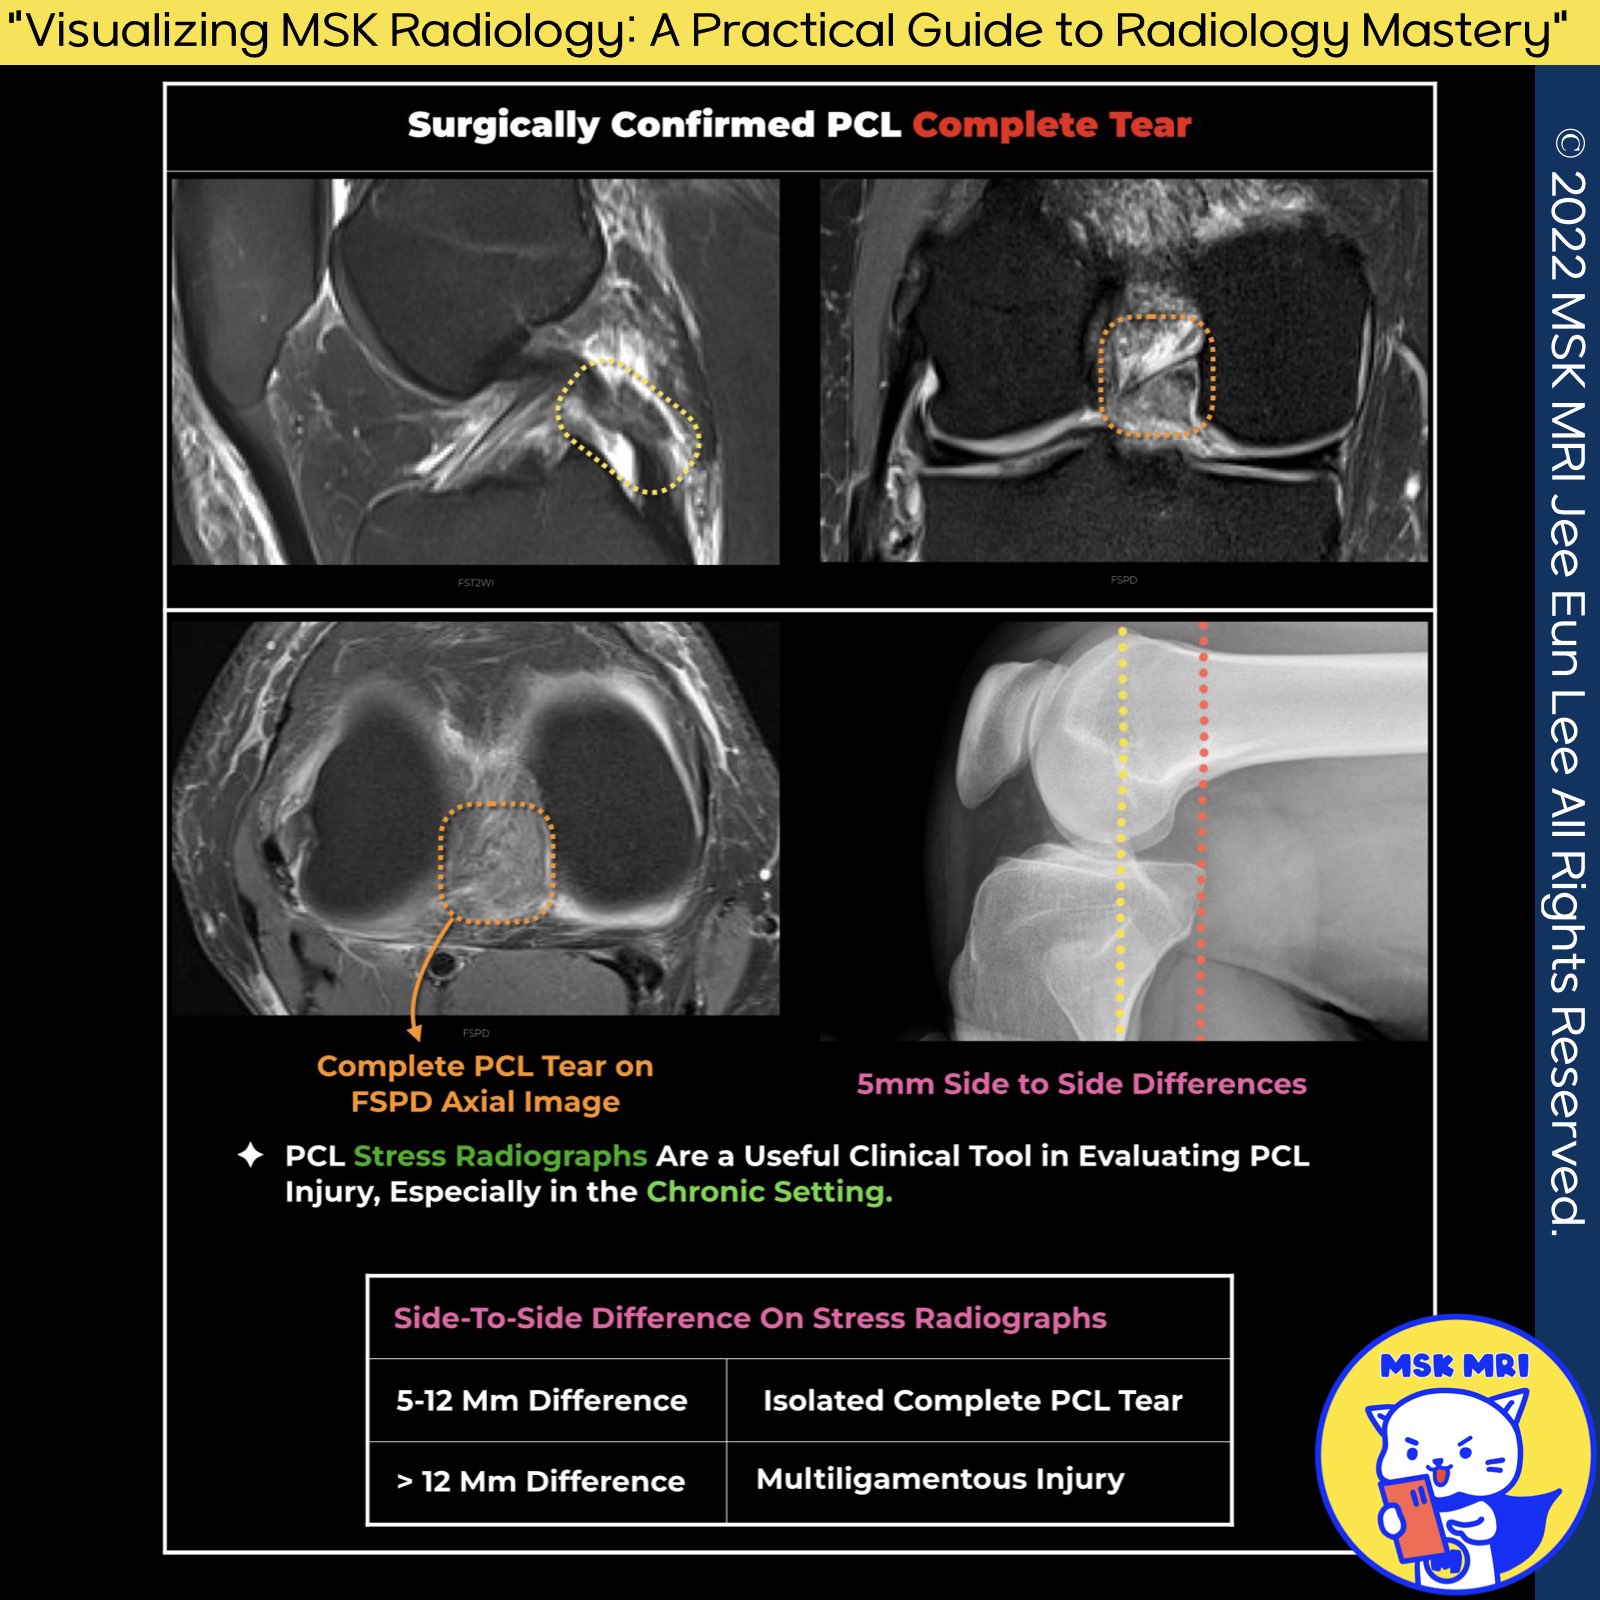

1️⃣ PCL Stress Radiographs in Chronic Injuries:

- Due to the healing process, MRI examinations in patients with chronic PCL injuries might not fully reveal the extent of the deficiency.

- Stress radiographs offer a more objective method to assess the PCL's structural integrity.

2️⃣Clinical Utility of PCL Stress Radiographs:

- These radiographs are useful clinical tools for evaluating the extent of PCL injury and determining the need for surgical intervention, especially in chronic conditions.

3️⃣Interpreting PCL Stress Radiographs:

- Method: Measurements are taken from the tibia's posterior cortex to the femoral condyles' posterior cortex, compared with the unaffected knee.

- Findings:

4️⃣ Enhanced Detection of PCL Injury with Proton Density Images

- Limitation of T2-Weighted Images: Sole reliance on these images may overlook subtle pathological changes in the PCL, resulting in decreased sensitivity.

- The advantage of Proton Density Images is that they offer enhanced visibility of abnormal intermediate or fluid intrasubstance signals, making them superior for detecting subtle PCL changes.